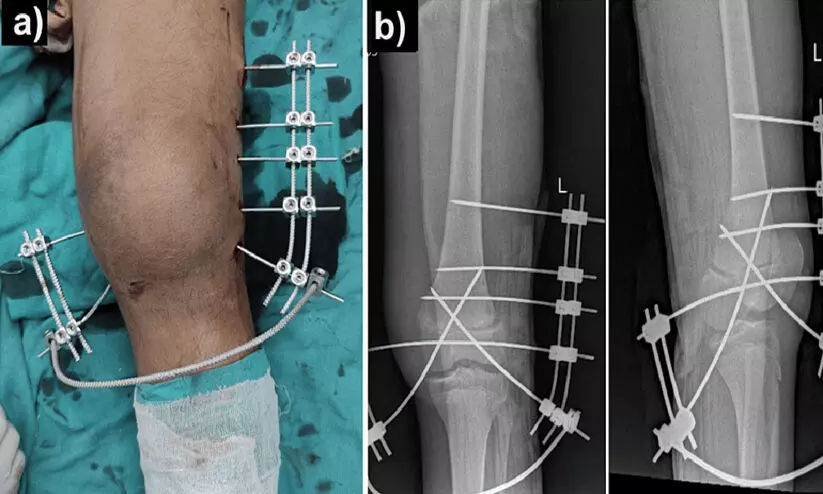

ആരോഗ്യ സംരക്ഷണവുമായി ബന്ധപ്പെട്ട അണുബാധകളിൽ ഏറ്റവും വ്യാപകമായ ഒന്നാണ് ശസ്ത്രക്രിയാ അണുബാധ. എല്ലുകൾ പൊട്ടിയാലും മറ്റും അകത്ത് കമ്പിയും സ്ക്രൂവും പോലെയുള്ളവ നിക്ഷേപിച്ചുകൊണ്ടുള്ള ഓപ്പൺ റിഡക്ഷൻ ഇന്റേണൽ ഫിക്സേഷൻ സർജറി, അകത്തും പുറത്തുമായി ഇവ ഉറപ്പിച്ചുകൊണ്ടുള്ള ക്ലോസ്ഡ് റിഡക്ഷൻ ഇന്റേണൽ ഫിക്സേഷൻ സർജറി എന്നിവയിലൂടെയുള്ള അണുബാധ നിരക്ക് 54.2 ശതമാനമാണെന്ന് ഇവർ കണ്ടെത്തി.